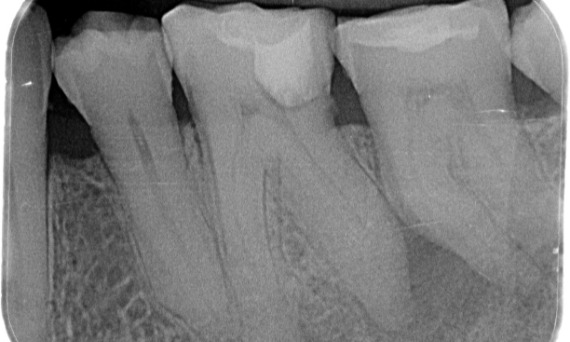

Prima: Radiolucenza periapicale associata principalmente alla radice distale e perdita della lamina dura sulla radice mesiale.

Dopo: TruNatomy è stata scelta in questo caso per consentire un approccio basato sulla carie e un’attenzione alla conservazione della dentina pericervicale, specialmente sull’aspetto mesiale in cui il dente aveva un restauro più minimo.